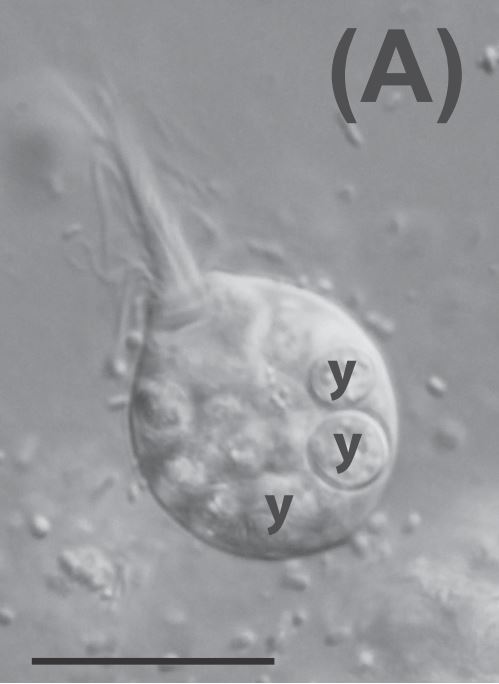

As it turns out, the differences between true Lophomonas and human epithelial cells are not subtle at all. Consider the following figure. The first three panels (A-C) show Lophomonas blattarum, and the second three (D-F) show human epithelial cells. Note the shape of the flagellar bundle in the anterior, the location of the nuclei (labelled “n”), and the overall appearance of the cell.

The video evidence is even more clear. The supplementary materials to the article include footage of genuine Lophomonas blattarum which can be downloaded and viewed. In that video, taken by Gillian Gile, a Lophomonas cell is seen moving purposefully forward, with the help of a narrowly concentrated tuft of flagella at the apex of the cell. Distinctive features of the cell, such as the axostyle and the calyx (both recorded by R. R. Kudo in the 1920s!), can be seen at certain points.